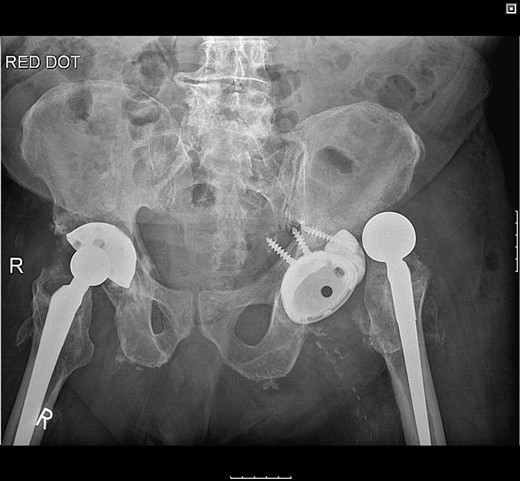

Pelvic radiographs demonstrated that the femoral head had migrated superolaterally through the polyethylene (PE) liner and the acetabular cup with metallic fragments inferior to this, and was articulating with the superior wall of the acetabulum causing bony destruction. There was no radiographic evidence of loosening to the stem (Fig. 1).

Pelvic radiograph demonstrating superolateral migration of the femoral head, metallic fragments around the neck and bony destruction of the acetabular wall.